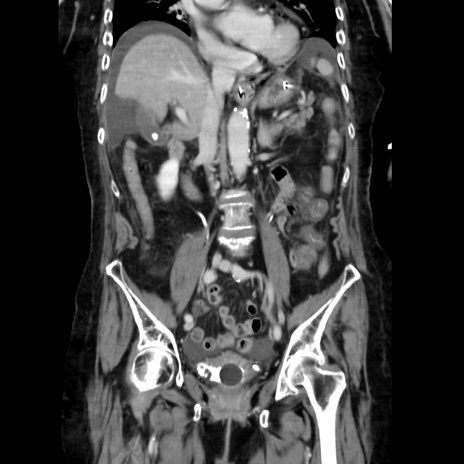

症例40(冠状断像)

【症例】90歳代女性

【主訴】腹痛・嘔吐

【現病歴】 食欲低下、嘔吐があり昨日他院受診。肺炎と診断され入院となる。入院後より腹部全体に圧痛あり。胃管留置され経過みていたが、症状持続するため、

当院転院となる。

【既往歴】胸椎圧迫骨折、胆石症

【身体所見】腹部:中央に激痛あり、圧痛あり、反跳痛不明

【データ】WBC 17100、CRP 18.82

冠状断像